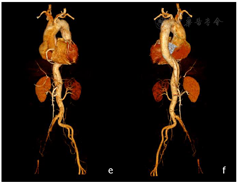

CTA图像显示:主动脉根部至双侧髂总动脉管腔呈双腔样改变(图a~b);两腔密度不一致,假腔大于真腔(图c~d),右侧髂总动脉、髂内外动脉显影明显差;腹腔干受累,显影差(图e~f)。

Ⅰ型主动脉夹层,夹层范围上自主动脉根部下至右侧髂内外动脉、左侧髂总动脉起始部,夹层累及右冠状动脉、头臂干、左颈总动脉、左锁骨下动脉、腹腔干及左肾动脉;右侧髂总动脉及髂内外动脉大范围受累显影差并血栓形成;左肾显影差。